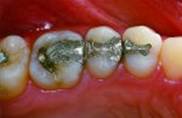

Tenho restaurações escuras (metálicas) nos dentes

posteriores.

Vale a pena trocá-las por restaurações de cor branca ou da

cor dos dentes?

A troca de uma restauração metálica por uma estética

ou, como dizem os pacientes, “por uma branca”, pode dar-se por

dois motivos principais: por problemas que envolvem a saúde do

dente, como uma fractura da restauração pré-existente ou mesmo

por recidiva de cárie (nesse caso, a troca não é discutida e

pode, perfeitamente, ser feita uma restauração estética), ou

por motivo exclusivamente estético.

Antes![]() |

Depois![]() |